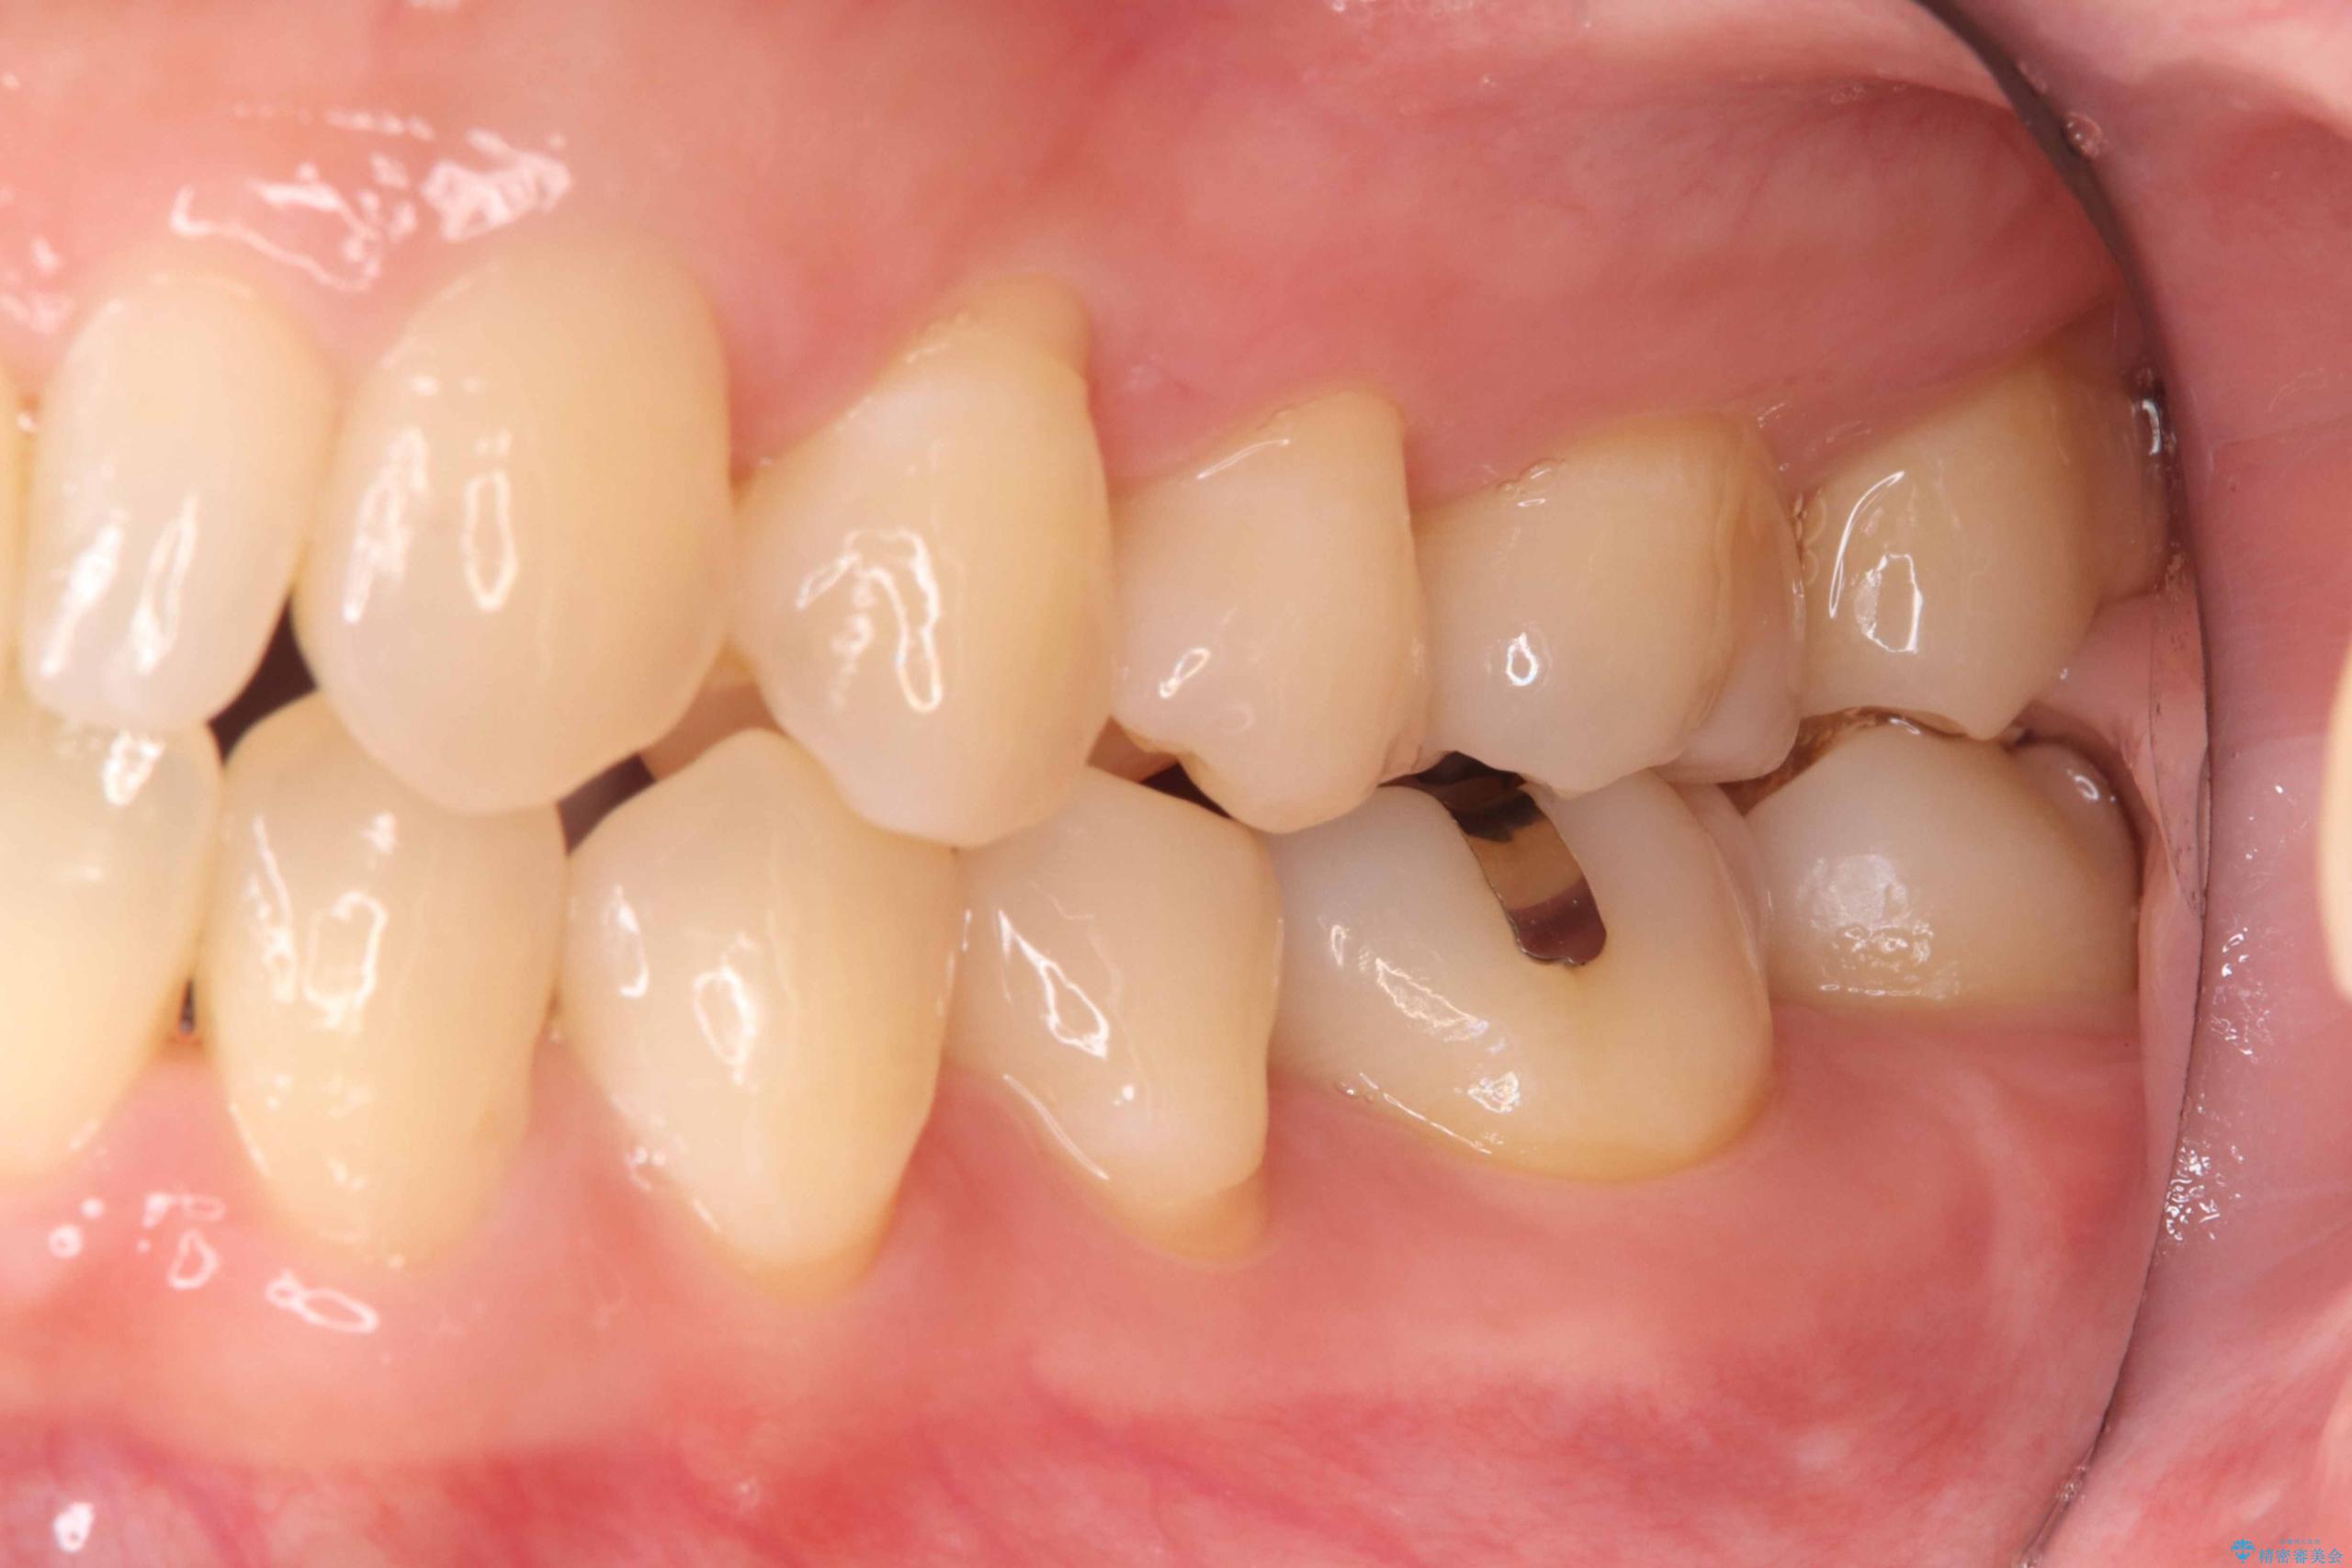

歯が欠けたことによるものか、もしくは以前装着された修復物の不適合が原因と考えられますが、銀歯(メタルインレー)と歯との間に大きな段差が認められ、汚れが溜まりやすい状態となっていました。

このような状態では、修復物の内部で虫歯が進行している可能性が高いため、治療が必要と判断しました。